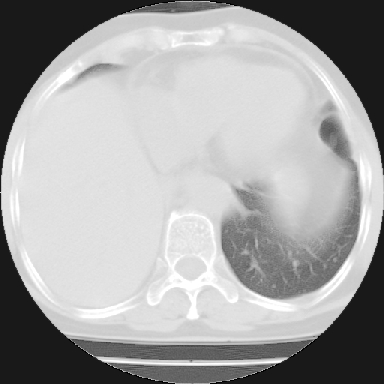

以下是引用苯小孩在2007-4-13 16:20:00的发言:[br]1、右下肺中央型肺癌并阻塞性肺不张、肺内转移、胸椎右侧附件亦有转移<横断层面第8层>.[br]2、右侧胸腔积液.

以下是引用swyyy2007在2007-4-13 15:31:00的发言:[br]右肺门下区肿块,右肺下叶支气管阻塞,右肺下叶不张,右侧大量胸腔积液,右肺中叶见结节状高密度影,边缘清,纵隔内见肿大淋巴结。首先考虑右下肺中心型肺癌伴右肺下叶不张、中叶、纵隔淋巴结转移。右侧胸腔积液。